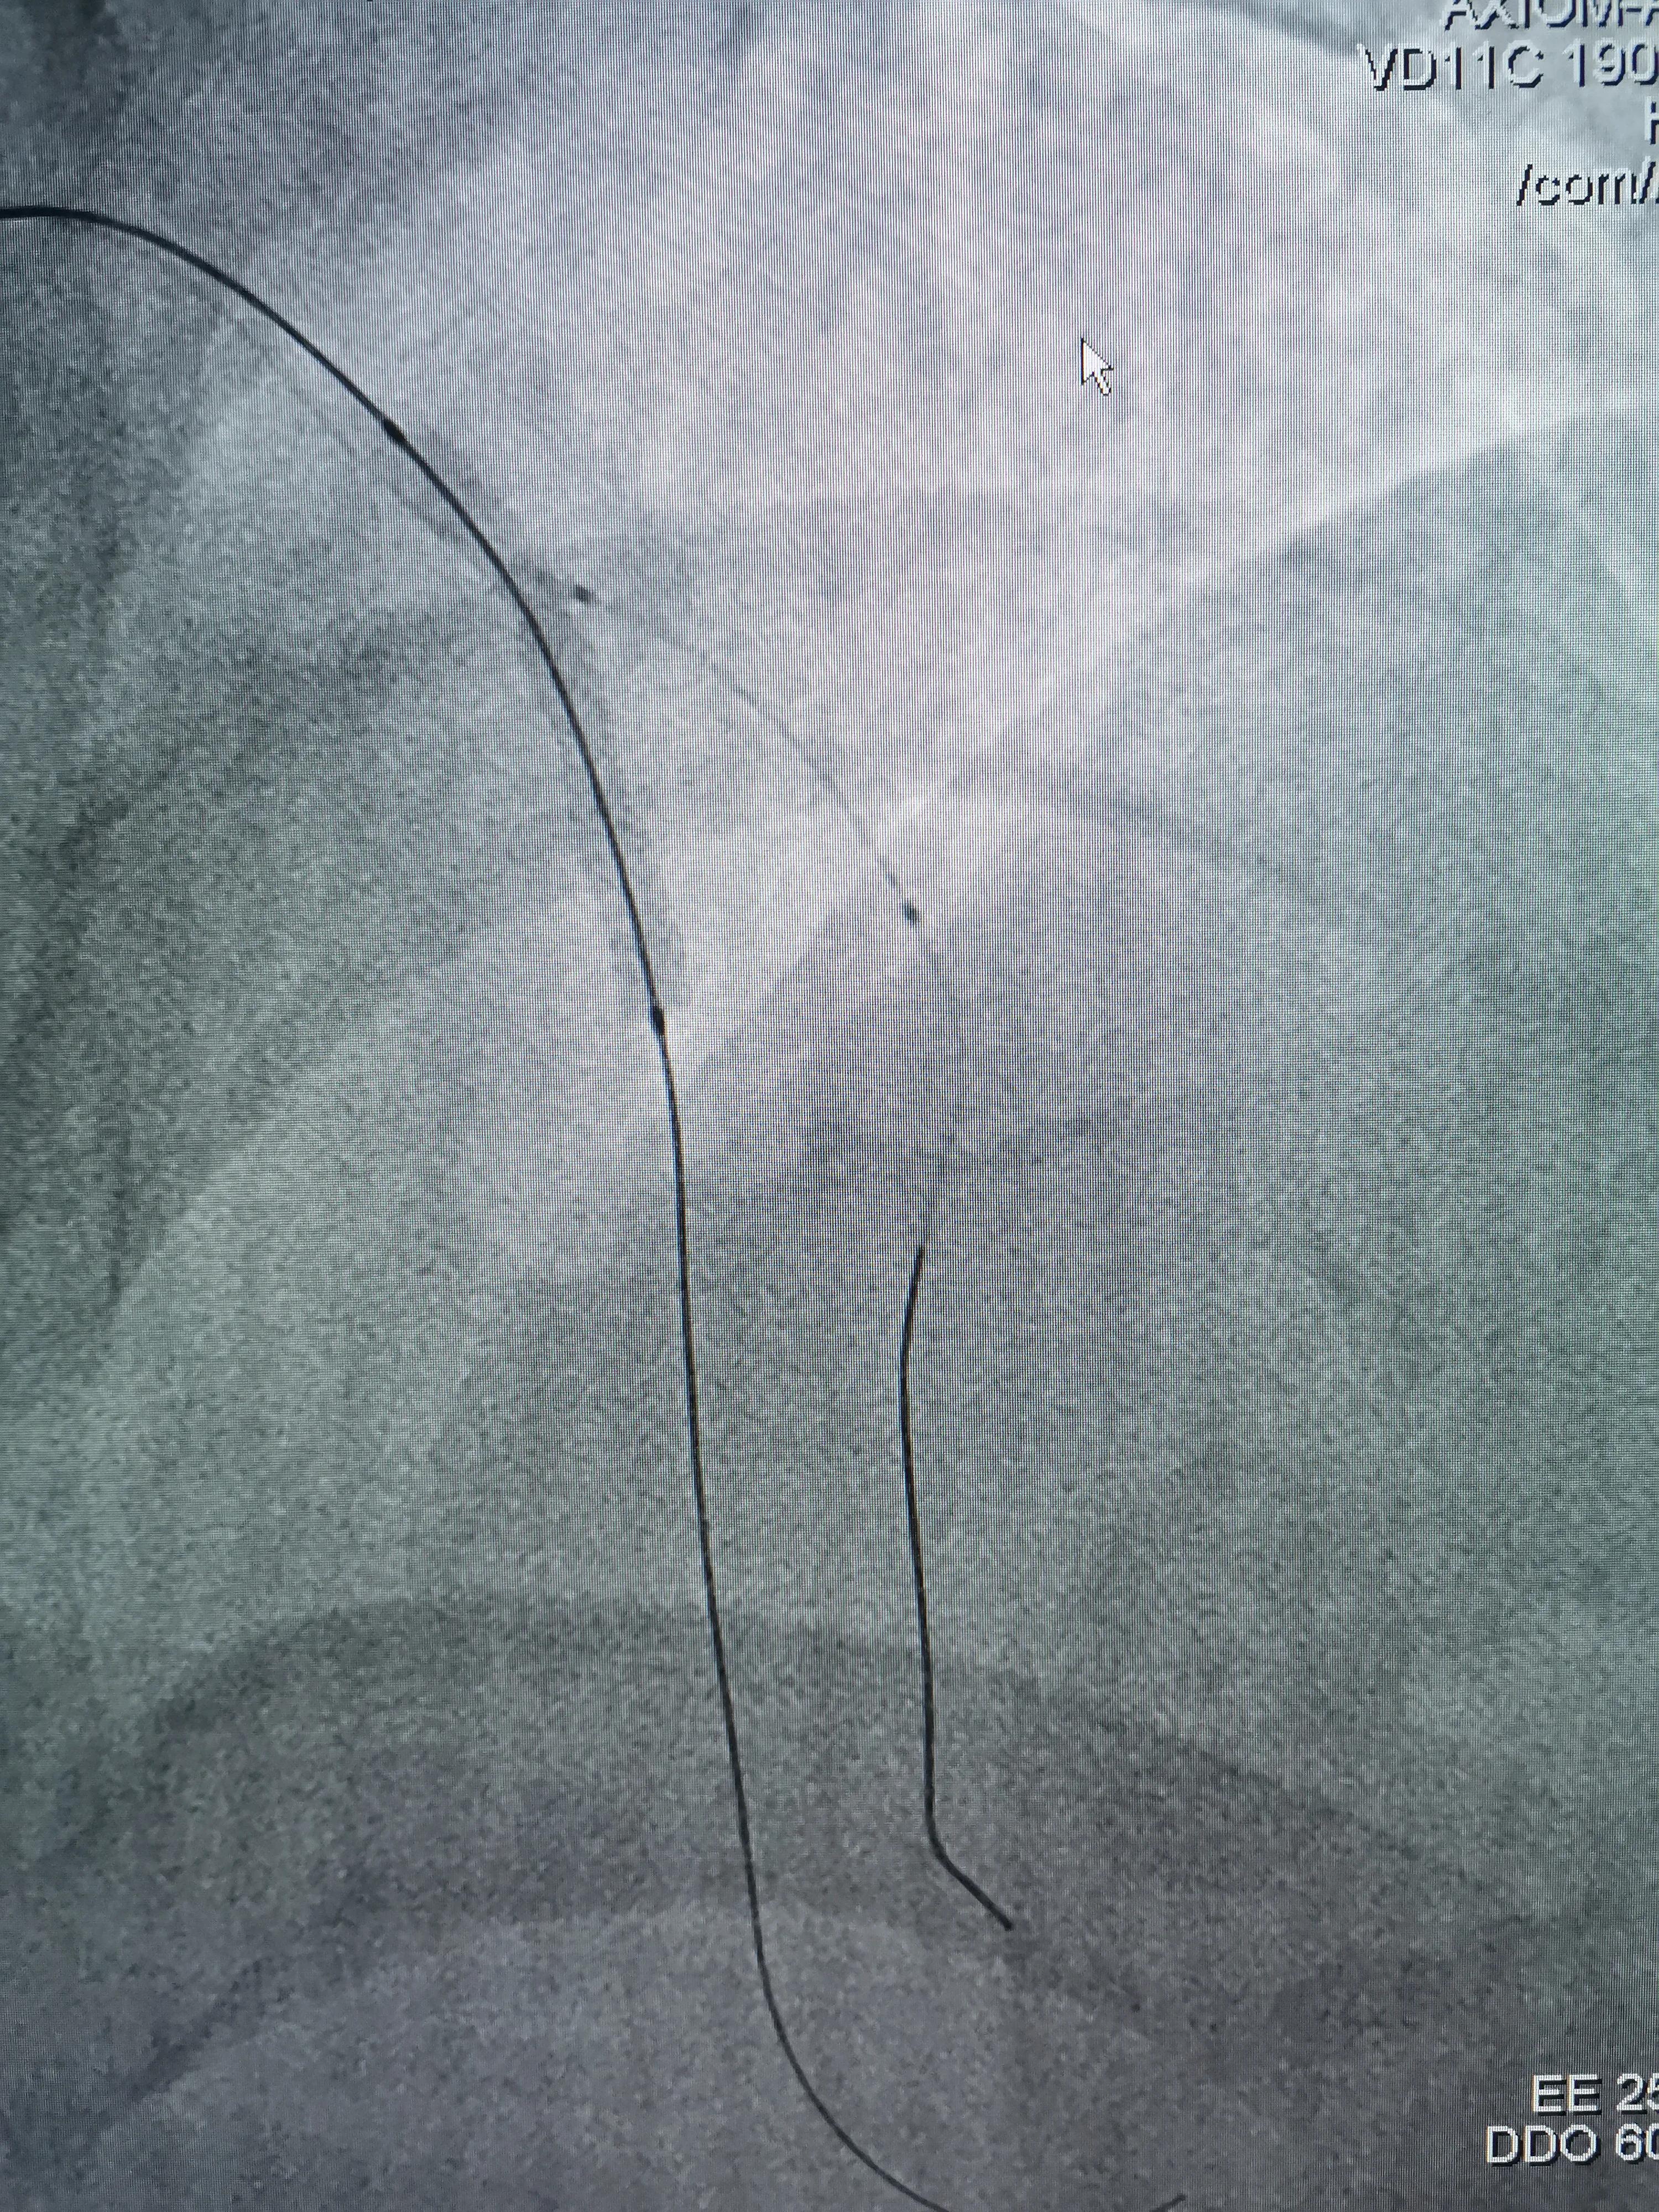

(支架预置LAD近段,D1开口到近段预埋球囊)

(支架球囊扩张,支架释放紧贴血管壁)